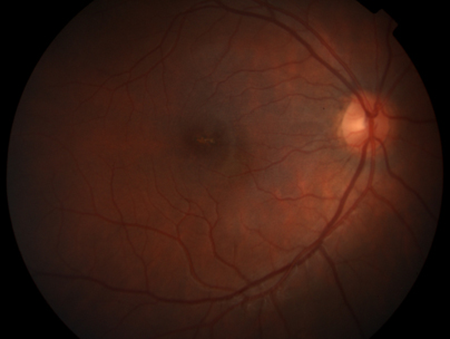

Al examen presenta AV mejor corregida de 20/60 en su ojo derecho (OD) y 20/40 en su ojo izquierdo (OI) en escala Snellen. El segmento anterior, cristalino y vítreo no presentaba alteraciones. En el fondo de ojos (FO) de AO se evidenciaron lesiones a nivel macular bien delimitadas de bordes irregulares amarillentos con centro grisáceo, resto sin particularidades (Imagen 1).

Imagen 1 - Ojo izquierdo Imagen 1 - Ojo derecho